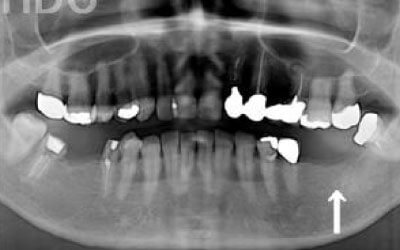

2 歯が傾いてくる、落ちてくる

歯はお互いに支え合ってバランスを保っています。つまり、歯が抜けるとその支えがなくなり、抜けた部分の隣の歯が傾いたり、上の歯が下にずれてくることがあります。